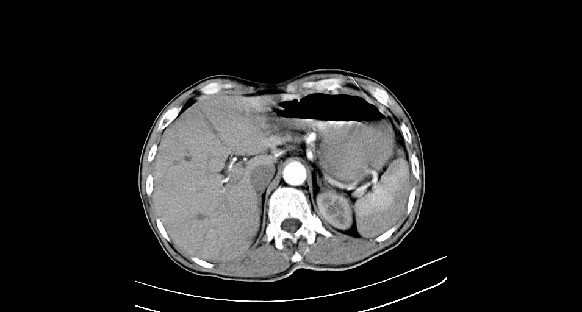

男性,70岁,体检b超发现左肾占位,请各位战友发表一下观点

左肾有两个病灶,且较大的病灶内可见点状钙化灶,增强扫描边缘也是呈渐进性强化,中央部分未见明显强化